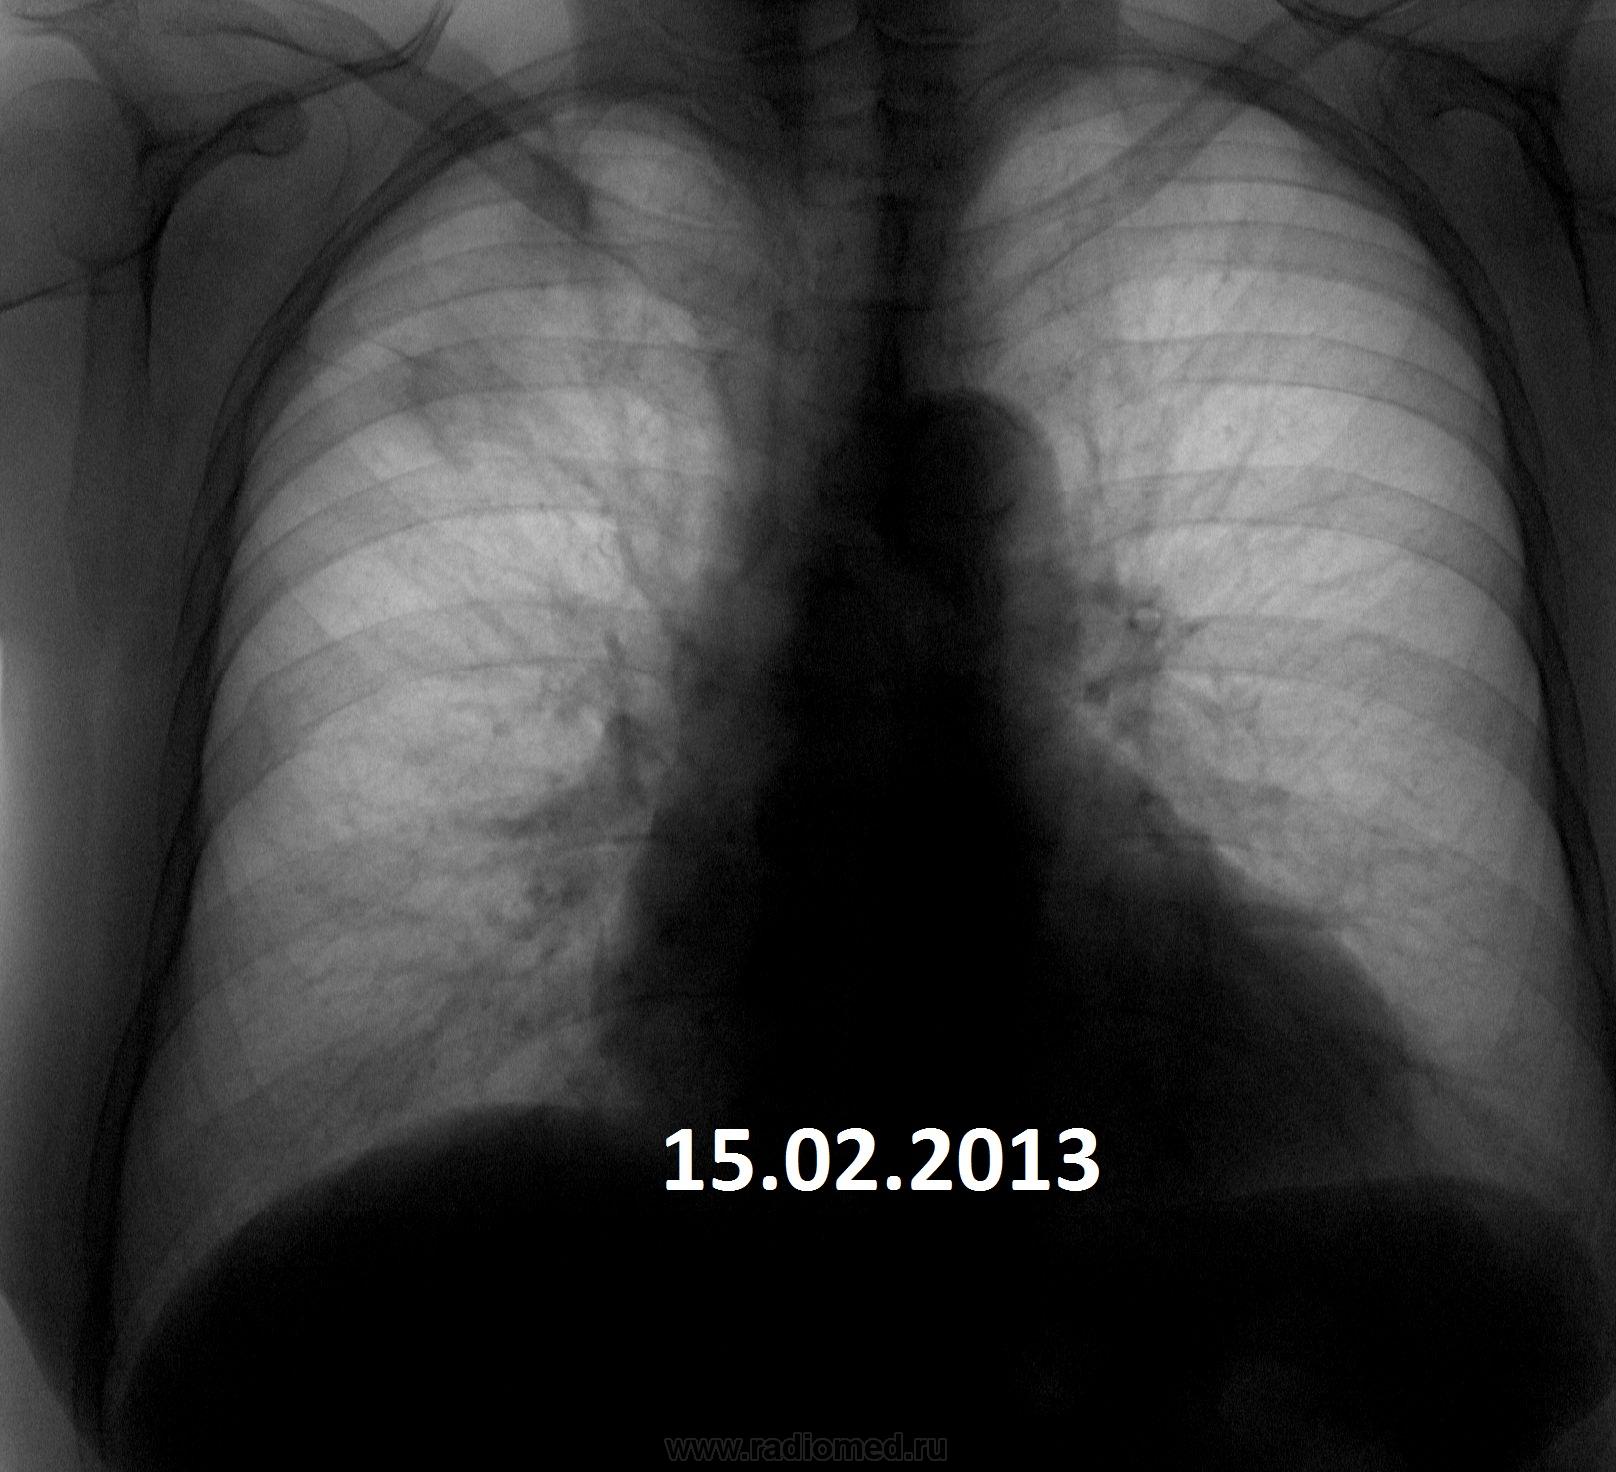

Пожилая опрятная женщина, жалоб нет, просит "отпустить". В феврале фтизиатры написали пневмонию. Сжалился - написал что-то вроде плеврофибрознотакая-то хрень.

• https://radiomed.ru/sites/default/files/styles/case_slider_image/public/user/3055/1937g.r.15.02.2013.jpg?itok=i_3tla_q

Коли фтизиатры отпустили так на них и грех.Сопоставляя с архивом от туберкулёза не отмахнёшся.

Но ведь не может туберкулез меделенно развиваться 4 года?

имеет место. Томографировать надо обязательно.

Не надо сбрасывать со счетов и левую верхушку.

Увы! Мне кажется - справа имеет место рецидив. Валентин Львович не зря на левую верхушку обратил внимание.

На первом месте- Tbc.

На втором: Если в легком неясная картина - ищи БАР.

В любом случае ТМГ.

+1. Не пневмония это точно. Прогресс слишком долгий. Больше склоняюсь к онко.

Я за онкологию